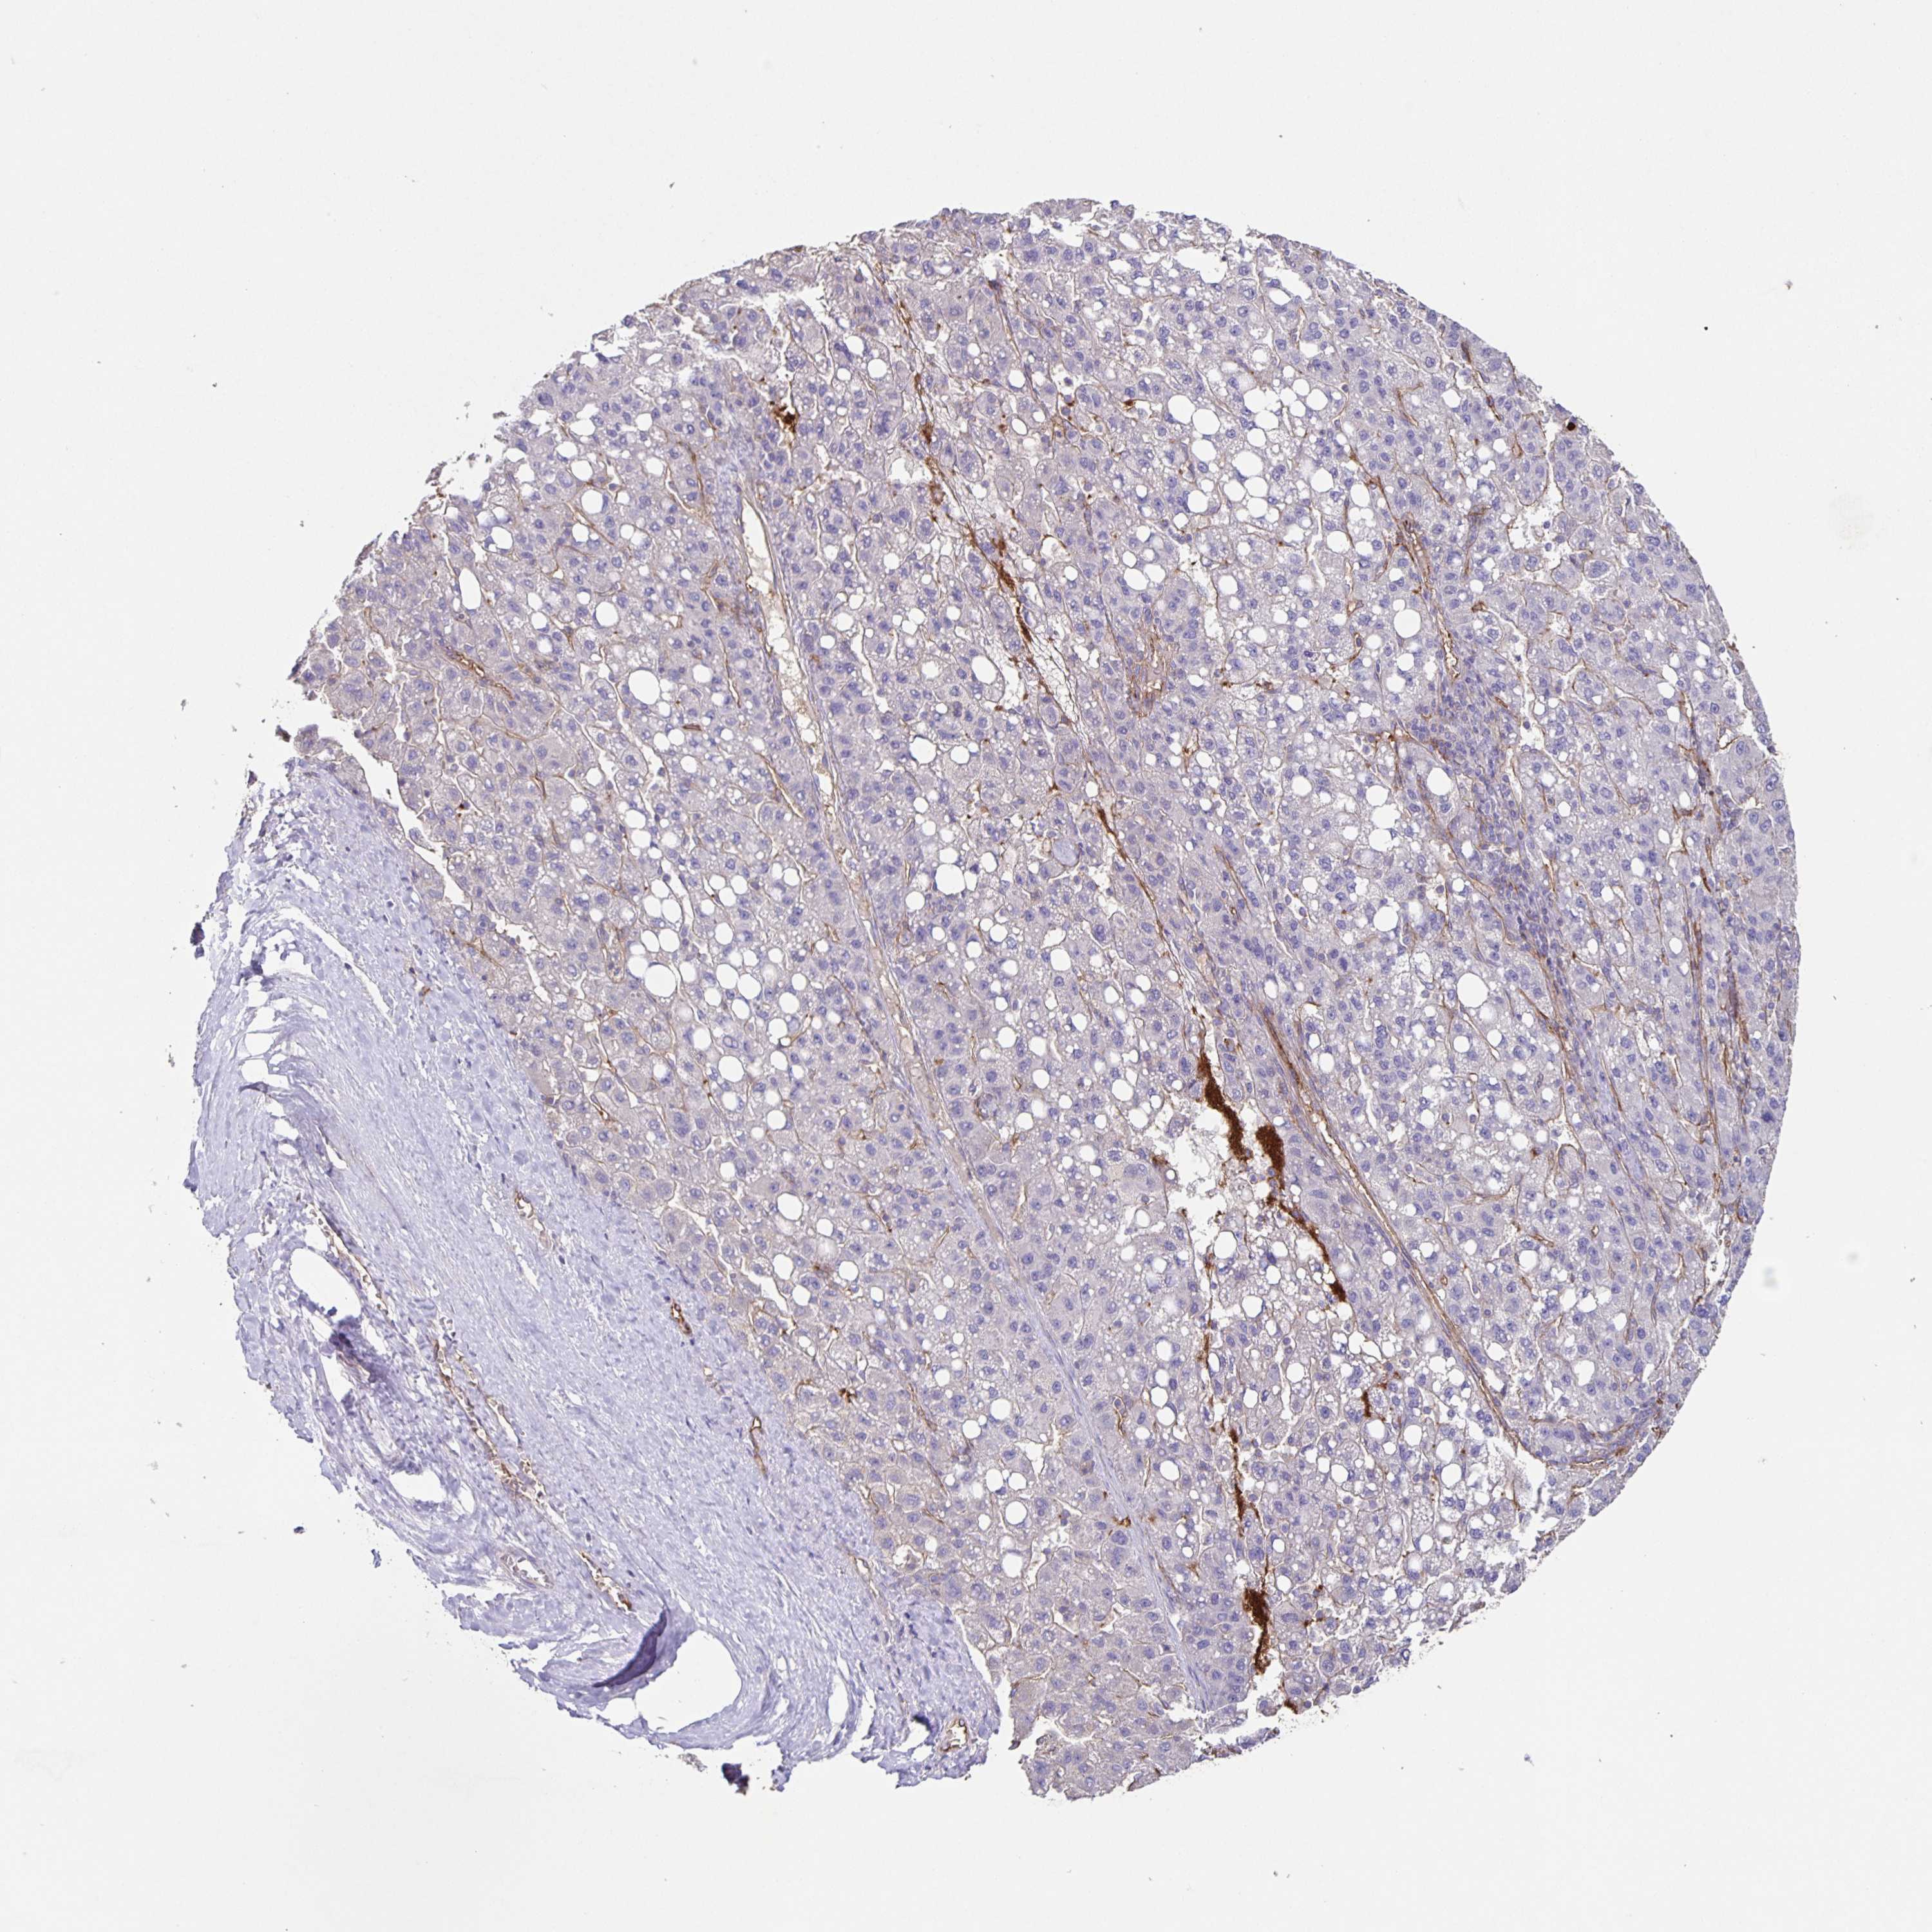

LIVER CANCER - Protein expressioni

A mouse-over function shows sample information and annotation data. Click on an image to view it in a full screen mode. Samples can be filtered based on level of antibody staining by selecting one or several of the following categories: high, medium, low and not detected. The assay and annotation is described here.

Note that samples used for immunohistochemistry by the Human Protein Atlas do not correspond to samples in the TCGA dataset.

Antibody stainingi

Antibody staining in the annotated cell types in the current human tissue is reported as not detected, low, medium, or high, based on conventional immunohistochemistry profiling in selected tissues. This score is based on the combination of the staining intensity and fraction of stained cells.

Each image is clickable and will lead to virtual microscopy that enables deeper exploration of all samples and also displays staining intensity scores, fraction scores and subcellular localization as well as patient and tissue information for each sample.

Antibody HPA060991

Antibody HPA063556

Antibody CAB017690

Staining

High

Medium

Low

Not detected

Intensity

Strong

Moderate

Weak

Negative

Quantity

>75%

75%-25%

<25%

None

Location

Nuclear

Cytoplasmic/membranous

Cytoplasmic/membranous,nuclear

Carcinoma, Hepatocellular, NOS

Cholangiocarcinoma